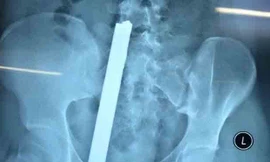

TPO - Nghe lời đàm tiếu của bạn bè về việc T. "không thích" mình, nên T.T.T.N đã dùng dao đâm 3 nhát vào vùng bụng, khiến T phải nhập viện cấp cứu.